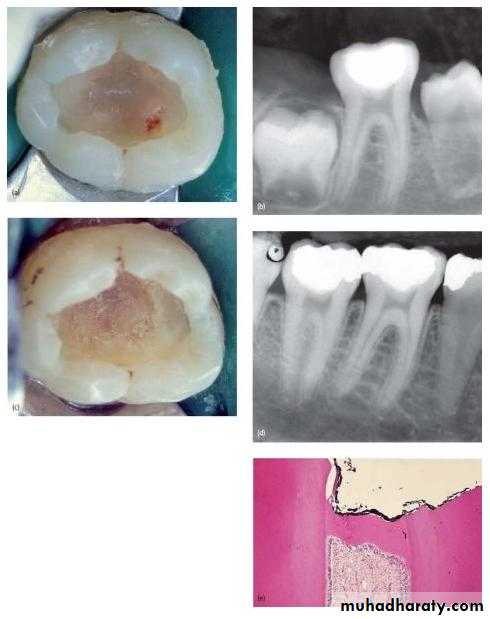

• Deep carious lesion in mandibular molars without pulp involvement.

• CLINICAL PROCEDURE

• It could be performed as a single or two step approach.

• Objective of this technique is to arrest carious lesion progression and allow formation of reparative dentin.

PROCEDURE

• FIRST APPOINTMENT

• Use of local Anesthesia and isolate with rubber dam.• A slow speed hand piece with round burs is used to remove the superficial debris and majority of soft infected dentin without exposing the pulp.

• Deepest layer of infected dentin is covered with a hard setting calcium hydroxide preparation and sealed with an overlying base of reinforced zinc-oxide eugenol preparation.

• This sealed cavity is not disturbed for 6-8 weeks.

• SECOND APPOINTMENT.

• The previous remaining soft, deep, brownish red affected dentin will have changed to lighter brownish gray colour and most importantly harder in nature.

• The entire floor is covered with calcium hydroxide preparation.

• When clinical and radiographic findings are negative the final restoration is placed.

• RESULTS-BEFORE

• AND AFTER• FACTORS DETERMINING SUCCESS OF IPC.

• Remaining dentin thickness(0.5-2mm)• Choice of indirect pulp capping agent.